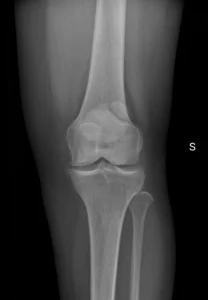

Consulta por dolor anterior de la rodilla. Sin antecedentes de trauma.

Las radiografias ap y oblicuas muestran Se identifica un fragmento óseo accesorio adyacente a la rótula, típicamente en el cuadrante superolateral, con bordes lisos y corticalizados, compatible con rótula bipartita (fallo de fusión de un centro de osificación).

El valor de este caso es evitar un error muy frecuente: confundir rótula bipartita con fractura.

Pistas a favor de rótula bipartita:

Ubicación típica superolateral (la más frecuente).

Bordes redondeados y corticalizados (no “filosos” como en fractura aguda).

Ausencia de signos claros de trauma agudo en partes blandas (según contexto).

A veces es bilateral (si tienes el otro lado, puede ayudar).

La mayoría son asintomáticas, pero puede volverse sintomática (dolor anterior) sobre todo tras actividad o trauma; en ese caso, la RM puede mostrar edema de médula ósea cerca del fragmento, lo que apoya correlación clínica.